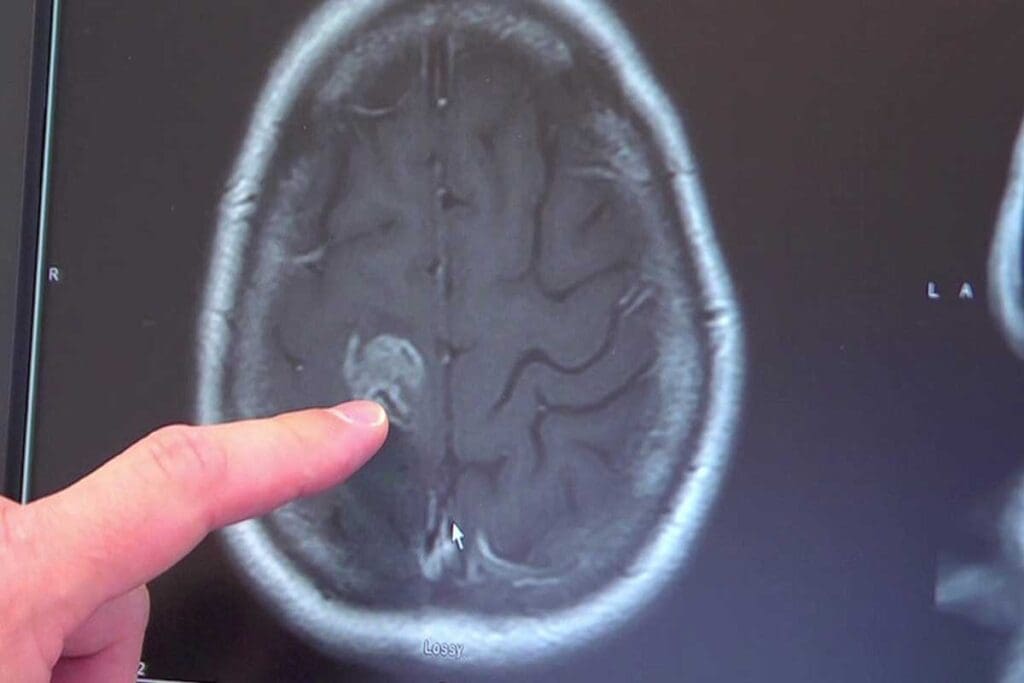

Cerebellum Brain Tumor Symptoms: Balance and Coordination Issues

Tumors in the cerebellum can greatly affect balance and coordination. The cerebellum is at the brain’s base and controls movement. A tumor here can cause serious symptoms.